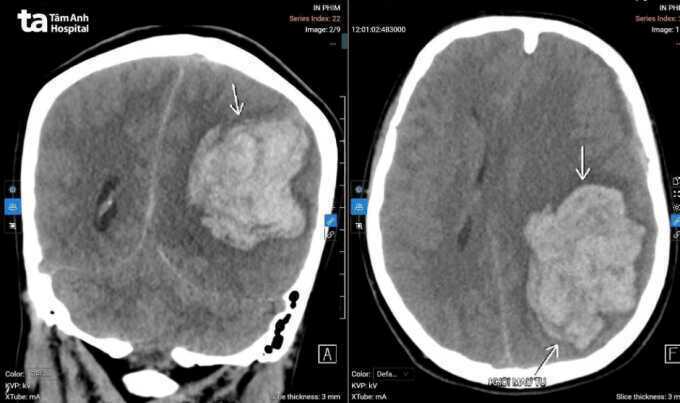

Loan cấp cứu tại Bệnh viện Đa khoa Tâm Anh Hà Nội trong tình trạng hôn mê sâu, mất phản xạ, chỉ số tri giác 6 điểm (người bình thường 15 điểm). Đồng tử trái giãn 4 mm mất phản xạ ánh sáng, đồng tử phải 3 mm đáp ứng yếu, liệt hai bên cơ thể. Kết quả chụp CT có khối máu tụ trong não cấp tính kích thước lớn tại bán cầu trái (khoảng 78×59×57 mm). Tình trạng phù não lan rộng, chèn ép lều tiểu não trái, thoát vị thái dương trong gây đè ép thân não. Lớp máu dưới màng cứng bán cầu trái dày khoảng 7,5 mm. Nguyên nhân chảy máu từ khối dị dạng mạch não.